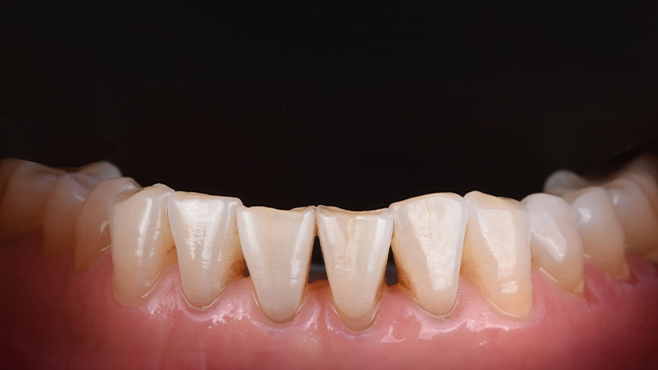

치과가 무서워 10년 동안 미뤄온 임플란트 수술 그 결과는?

2026.01.21